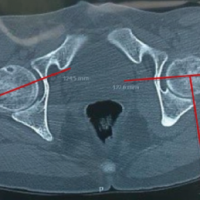

He was referred to the emergency department for vascular evaluation. Duplex Doppler ultrasound confirmed the diagnosis of a PA of the anterior tibial artery. The patient was admitted for surgical management, which consisted of ligation of the anterior tibial artery proximal and distal to the lesion (Fig. 3).

Figure 3: Ligation of the anterior tibial artery proximal and distal to the lesion.